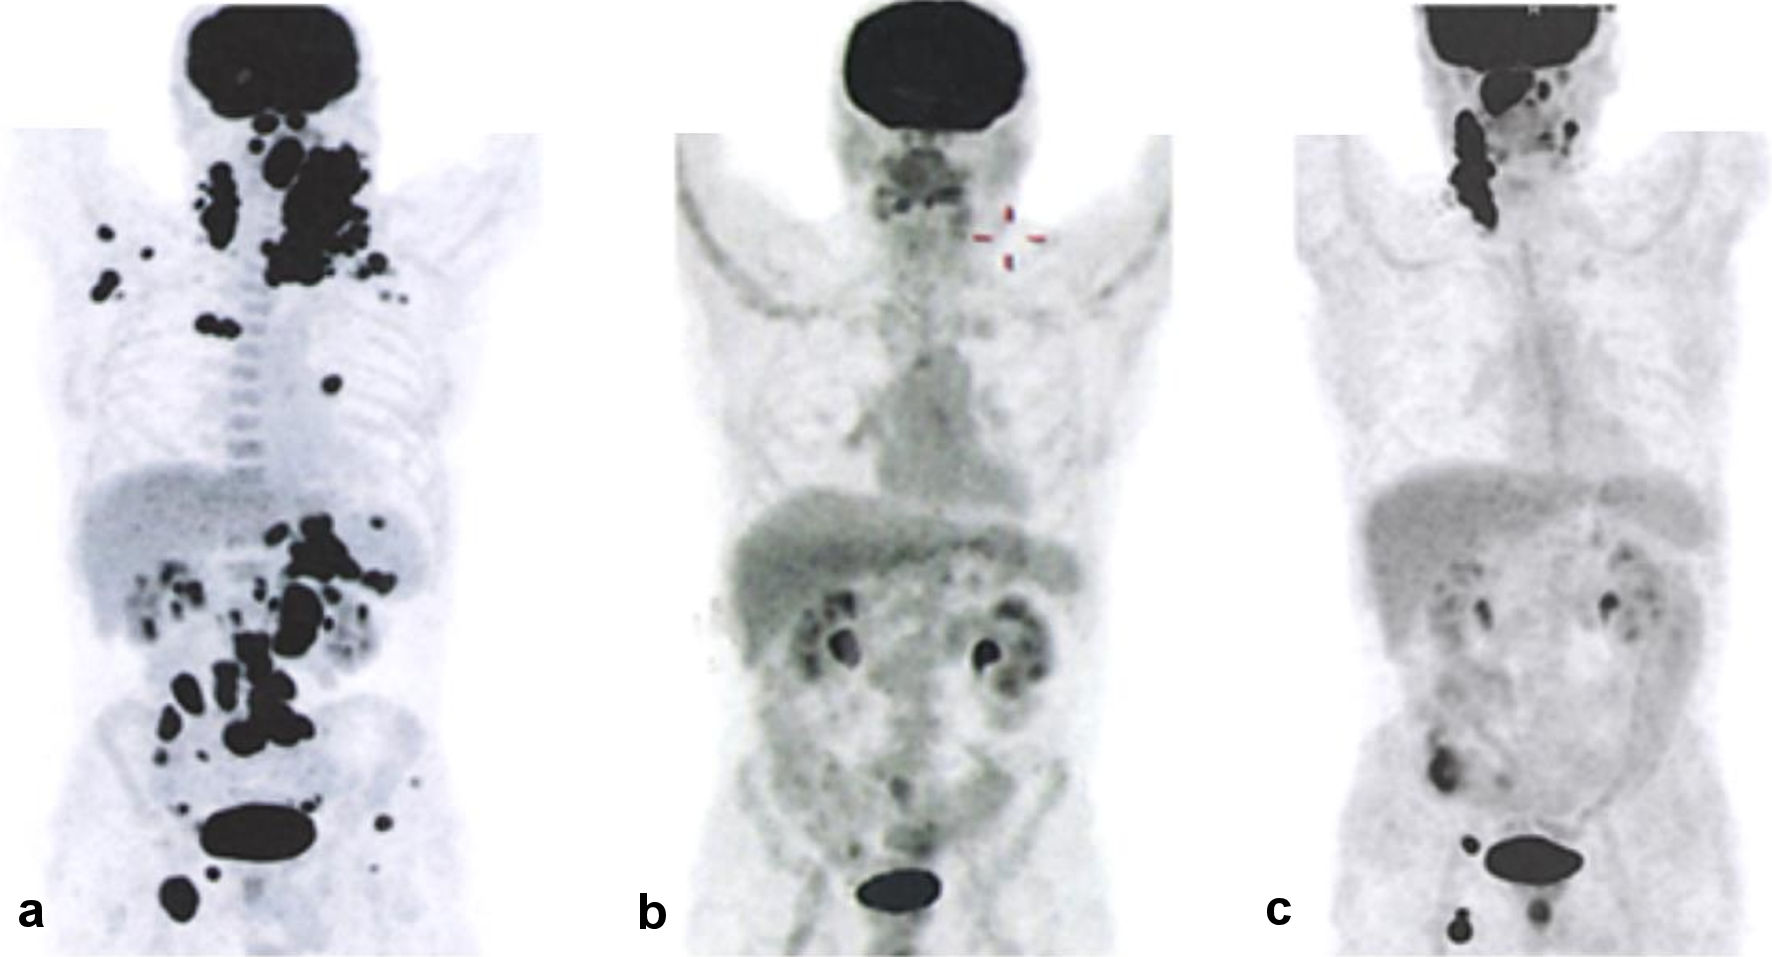

Non-GCB Diffuse Large B-Cell Lymphoma With an Atypical Disease Course: A Case Report and Clinical Exome Analysis